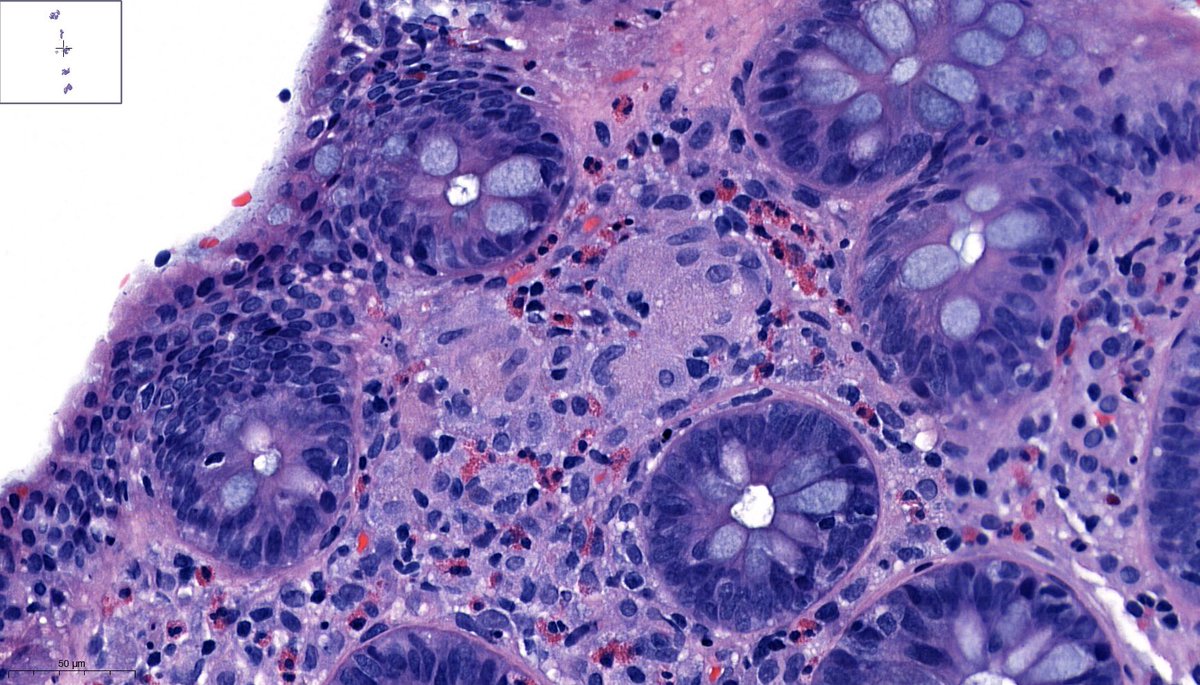

1/ A #GUpath case...TURB specimen with the following histology ๐Ÿ‘‡๐Ÿ‘‡๐Ÿ‘‡ Tumor at the urinary bladder neck. IHCs in the thread. Your dx? #pathology #PathTwitter